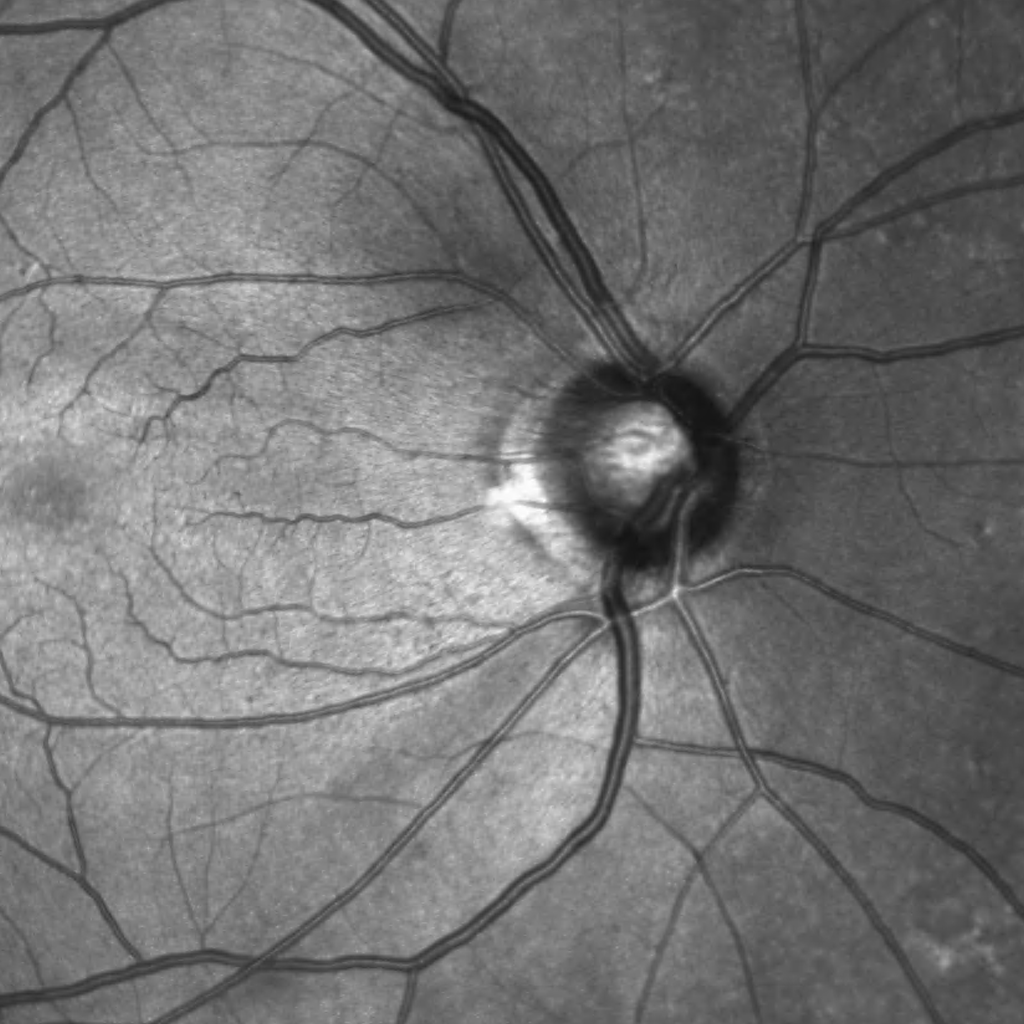

In dry AMD, these degraded products cannot be removed sufficiently, leading to a gradual build-up of waste products, so-called drusen, beneath the RPE cell layer. If the number and size of the drusen increase significantly over time, some RPE cells become damaged and may die. The photoreceptor cells above can no longer be adequately supplied with nutrients and can also die, leading to vision loss in this area. In its late stage, dry AMD is referred to as Geographic Atrophy.

The image illustrates changes in the macula such as cystoid changes and drusen.